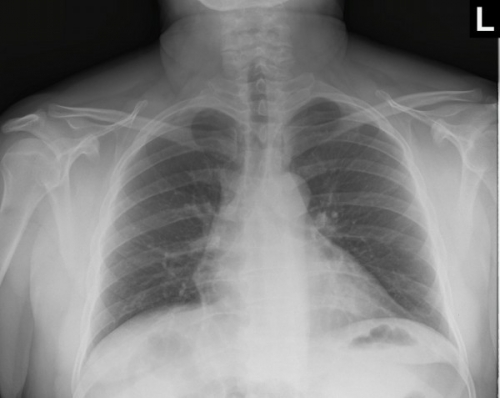

Tool to train medical student's eyes as to what a normal chest x-ray looks like, with over 500 consecutive normal images.